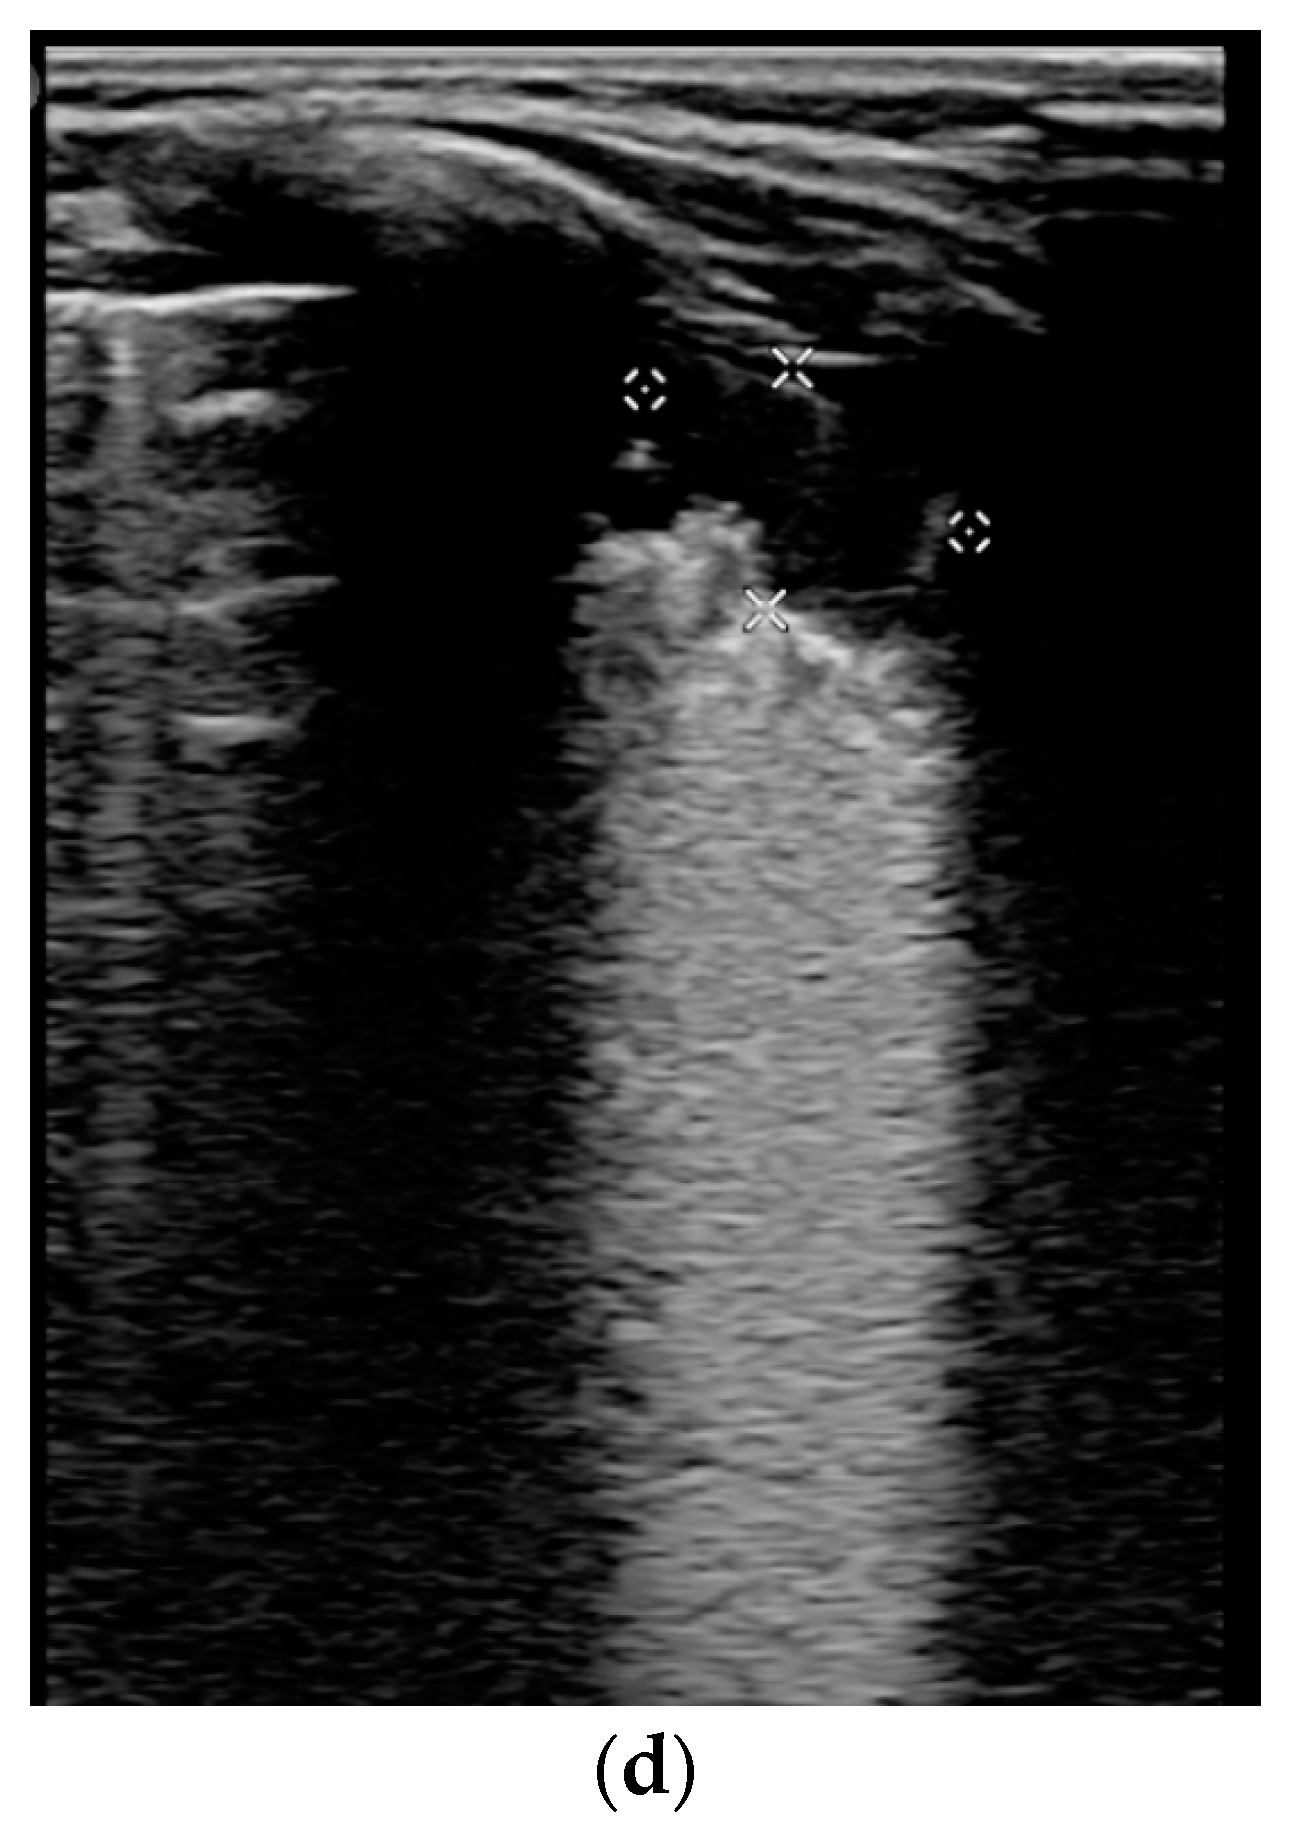

- Confluent vertical B-lines correspond to alveolar edema;

- Subpleural/peripheral consolidations;

| Normal/physiological A-lines | More than 2 B-lines (sparse B-lines) with associated pleural abnormalities | Coalescent or confluent B-lines | Large peripheral consolidation (wider than 1 cm) in association or not with air bronchogram |

| One or two B-lines per intercostal space | ‘White-lung’ aspect or small peripheral consolidation (smaller than 1 cm) |